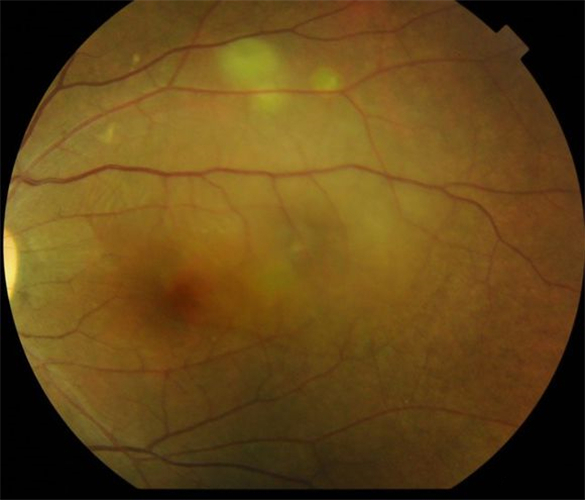

中心漿液性視網膜脫落